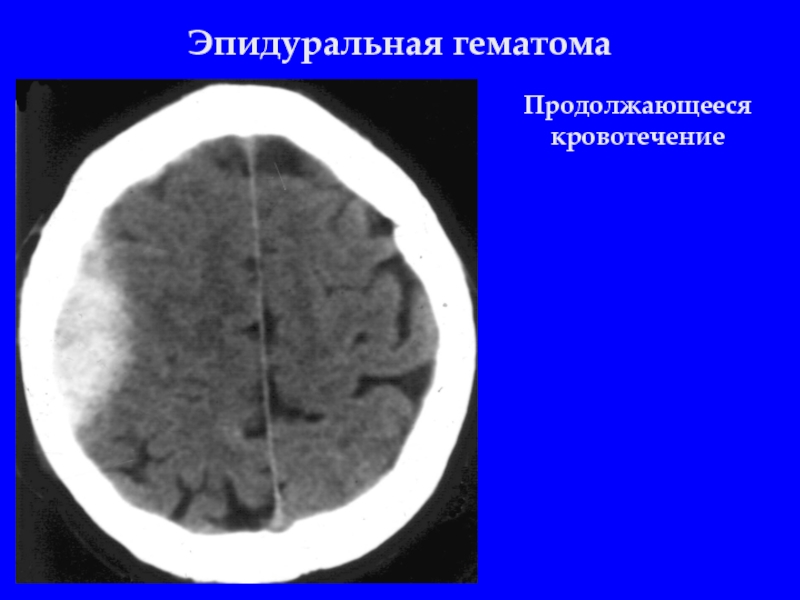

Слайд 10Эпидуральная гематома

Продолжающееся кровотечение, эффект седиментации